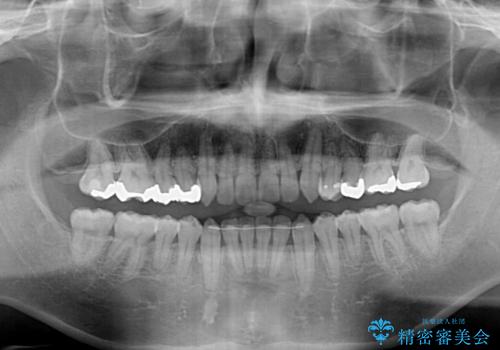

前歯のクロスバイト インビザラインによる矯正治療

インビザライン特有の、治療後半に奥歯が咬み合わないという事象が長引きました。

咬み合わないときの対処方法は色々とありますが、ゴムかけなどを活用して噛めるようにしました。